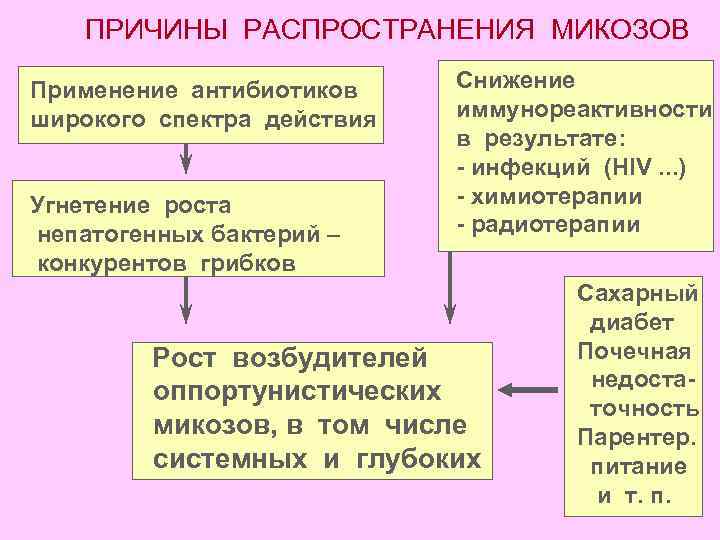

ПРИЧИНЫ РАСПРОСТРАНЕНИЯ МИКОЗОВ Применение антибиотиков широкого спектра действия Угнетение роста непатогенных бактерий – конкурентов грибков Снижение иммунореактивности в результате: - инфекций (HIV. . . ) - химиотерапии - радиотерапии Рост возбудителей оппортунистических микозов, в том числе системных и глубоких Сахарный диабет Почечная недостаточность Парентер. питание и т. п.